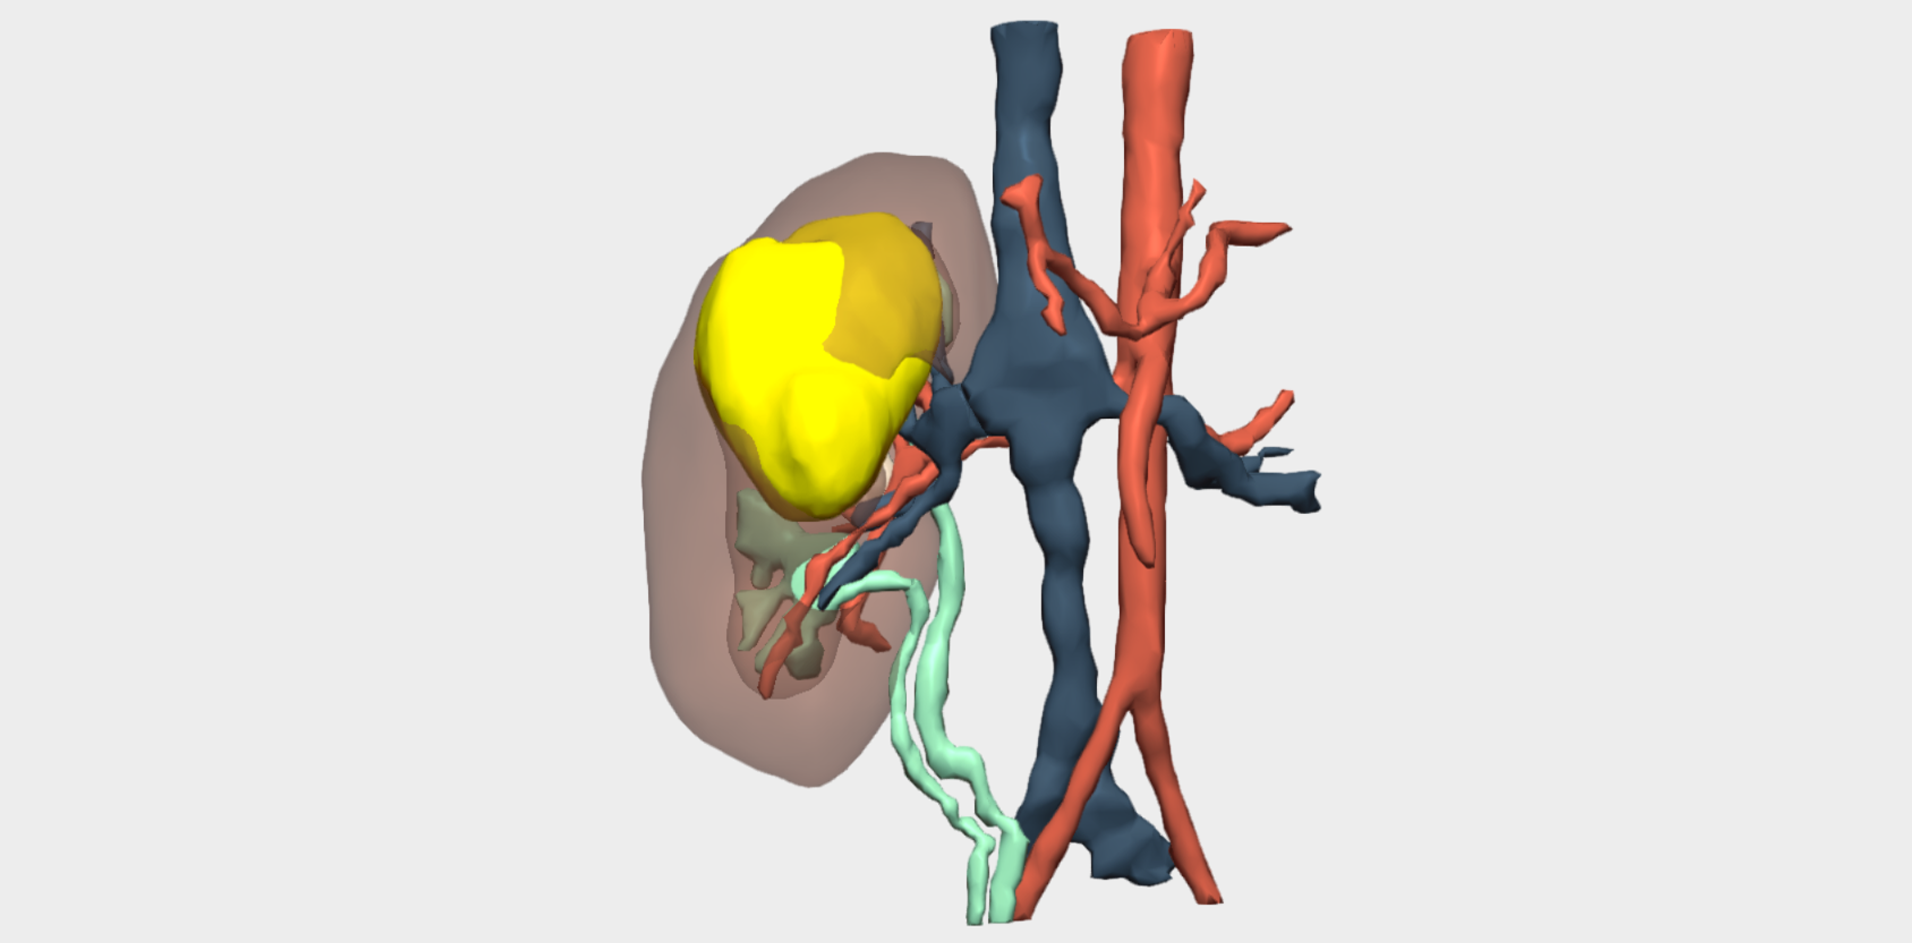

Following multidisciplinary assessment by the Oncology Committee, a right upper pole laparoscopic heminephrectomy was indicated for diagnostic histopathological analysis. Imaging studies were inconclusive and did not allow definitive diagnosis or exclusion of malignancy. Additional imaging performed at the Complejo Hospitalario Universitario de Albacete, including MRI and angio-CT, anticipated significant challenges in vascular localisation and dissection. The renal artery and vein bifurcated within the kidney, beneath the tumour and in close contact with it. Furthermore, the small calibre of these vessels limited precise visualisation of their anatomical course.

Three-dimensional reconstruction enabled precise localisation of the vascular bifurcation, revealing the presence of two arteries and two veins supplying each renal moiety —an anatomically relevant finding that had not been previously identified and was critical for surgical planning.

Detailed 3D anatomical analysis, combined with advanced functionalities such as arterial territory assessment and the ability to work intraoperatively with dual visualisation —3D reconstruction and laparoscopy displayed simultaneously— was a key factor in the success of the procedure.